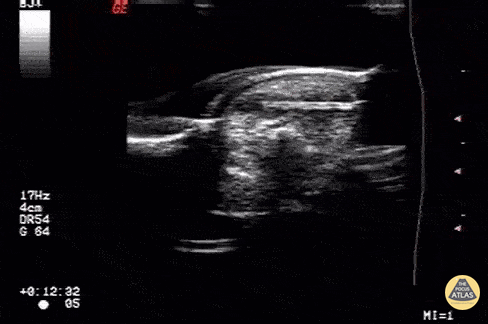

Trauma - Foreign body: wood piece

Alligator forceps being used to removed a retained wood piece within a fingertip Image courtesy of Robert Jones DO, FACEP @RJonesSonoEM Director, Emergency Ultrasound; MetroHealth Medical Center; Professor, Case Western Reserve Medical School, Cleveland, OH View his original post here